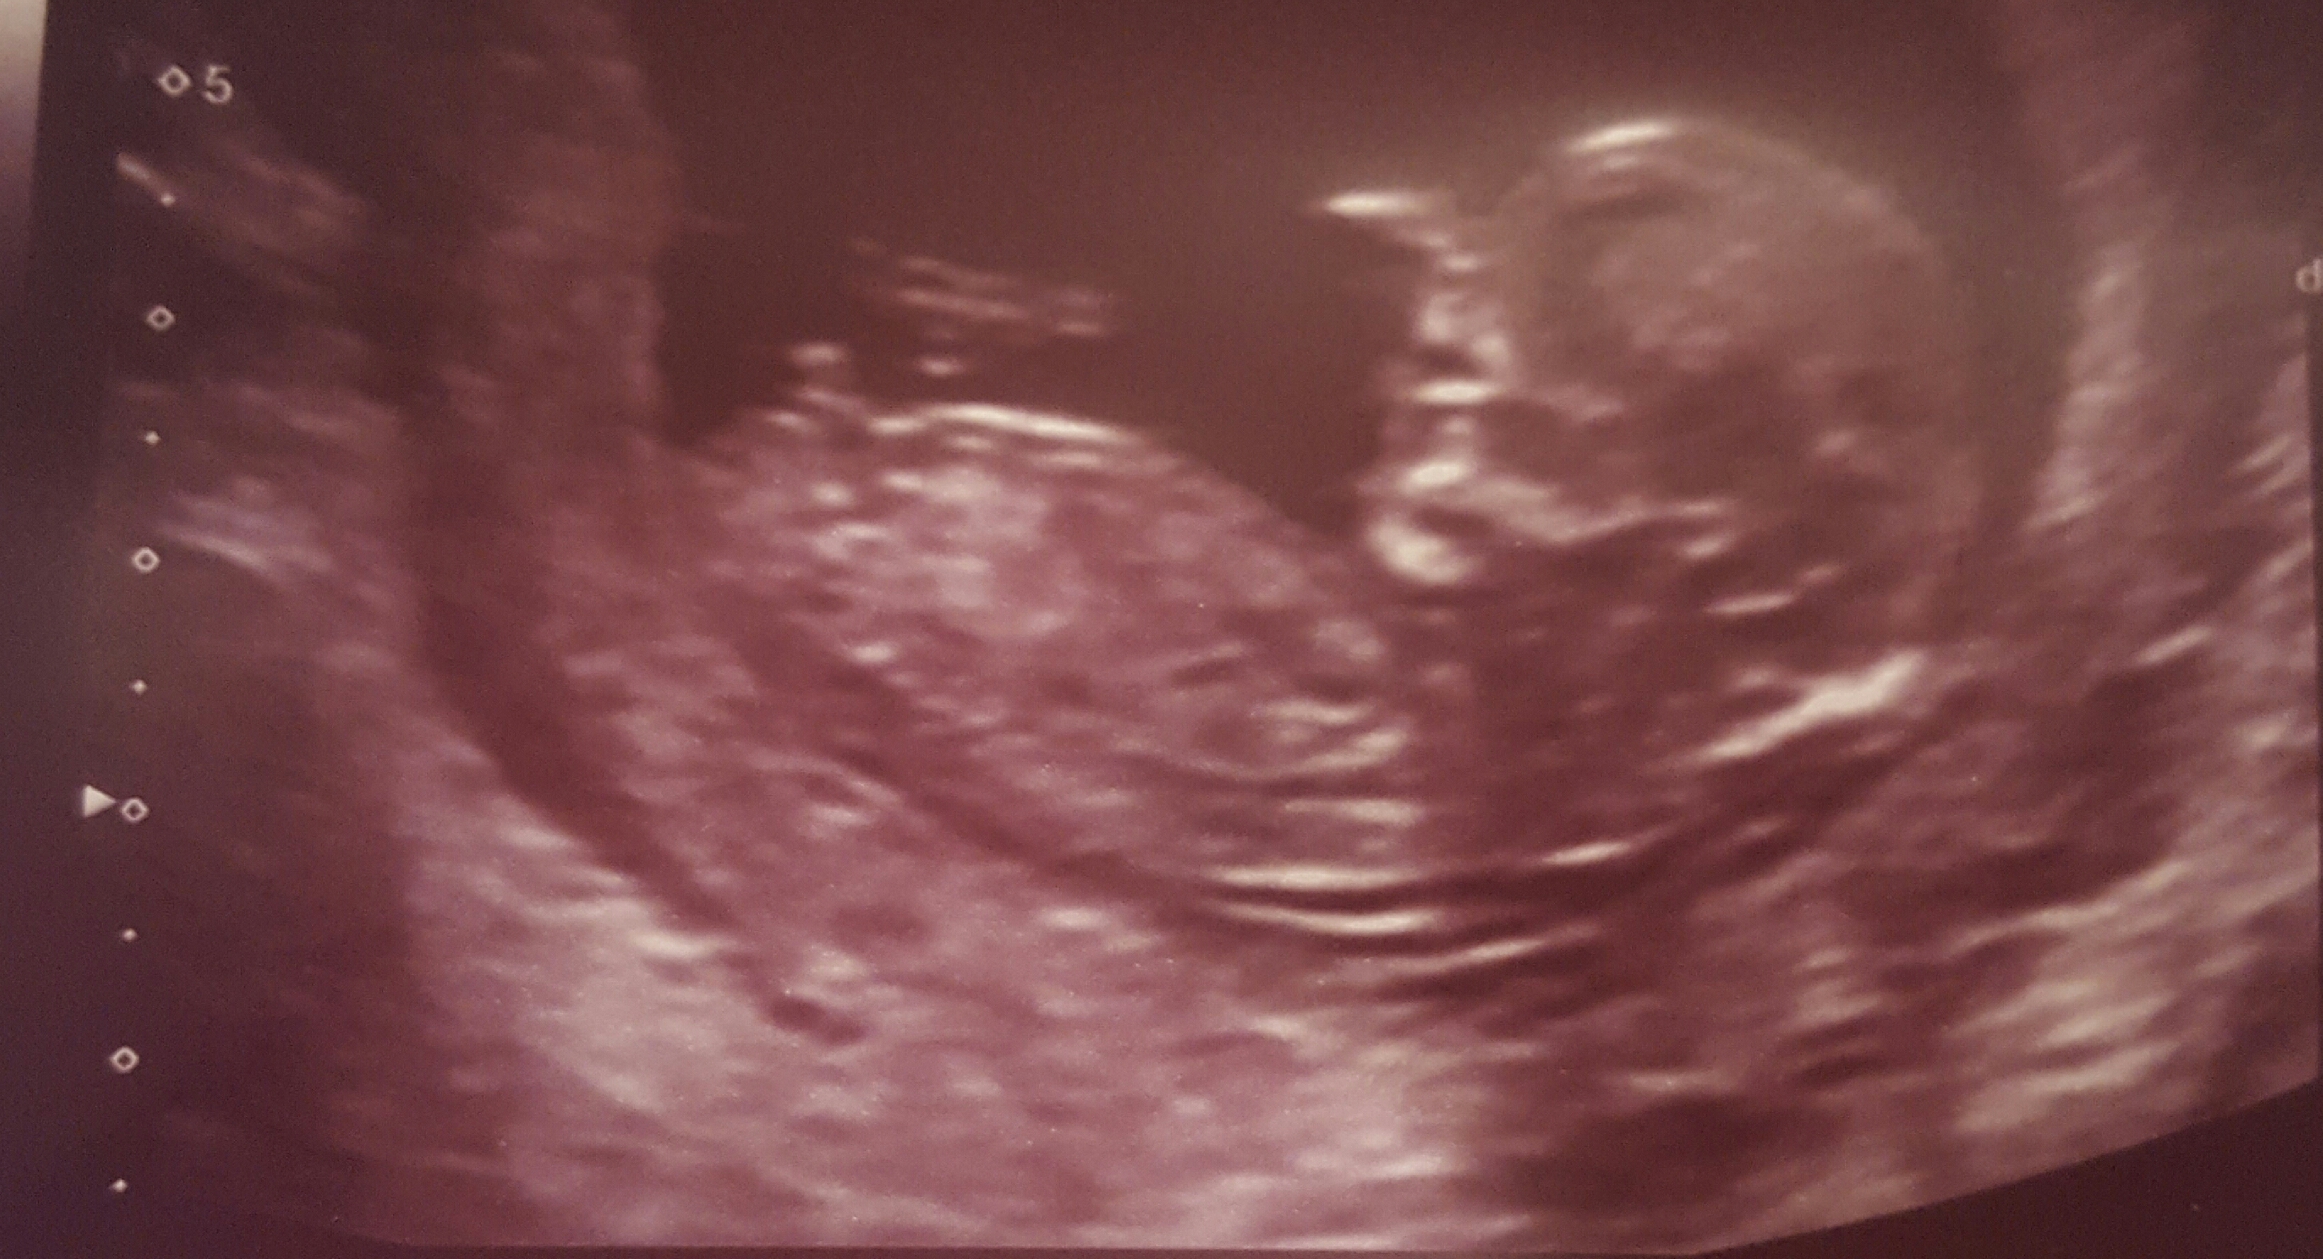

12 weeks 4 days.

Quite possibly a girl but it still could rise, I hope it's not some stacking I can see at the end and that you hear pink, good luck!

Looks girly so far good luck!

Slight girl lean. As others have said, there looks to be some stacking on the end.

The nub is not entirely visible on this pic. More pics? Video?